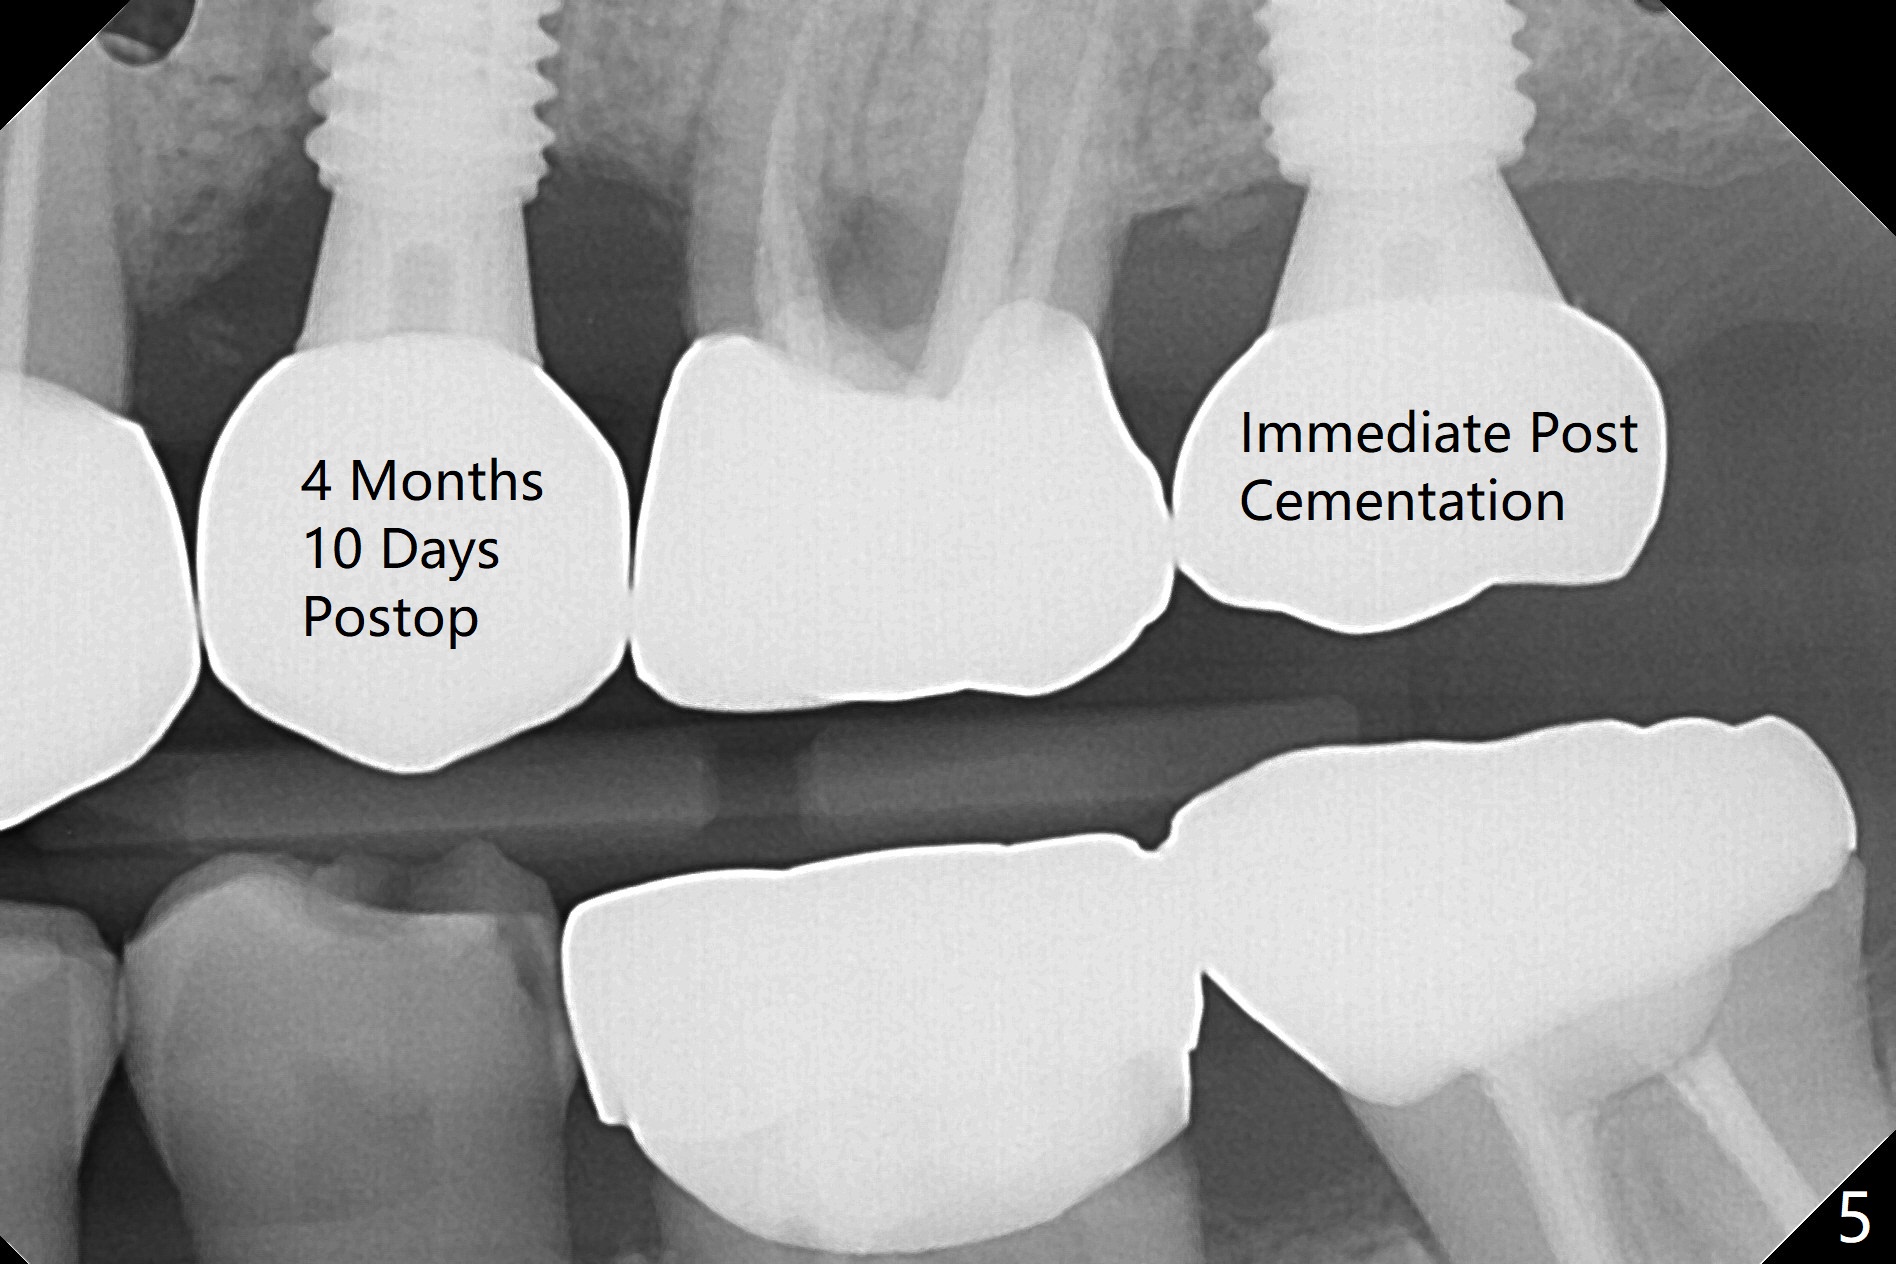

After underdrilling (3.5x14.5 mm drill (10.5 mm offset), a 4.5x11.5 mm implant is unable to enter the osteotomy at #13; following use of 4x10 mm drill (partial normal drilling), the implant is inserted smoothly with insertion torque ~ 35 Ncm. Sticky bone is placed in the bony portion of the buccal gap, while 2 pieces of PRF membrane in the gingival portion of the buccal gap. The bone density at #15 is low, the insertion torque is ~15 Ncm with normal drilling without cortical tap (Fig.1). The procedure is smooth in part due to no sinus involvement (red dashed line). An immediate provisional FPD is fabricated for #12-14. But local oral hygiene is difficult to maintenance. When the wound heals at #13, the FPD is removed. The bone loss is minimal nearly 4 months postop; the abutment at #13 is incompletely seated (Fig.2 arrowheads: gap). After repositioning, the abutment is re-seated completely without gap (arrowheads); a 5.7x4(3) mm cemented abutment is placed at #15 (Fig.3,4). Four crowns are cemented 4 months 10 days postop (Fig.5).